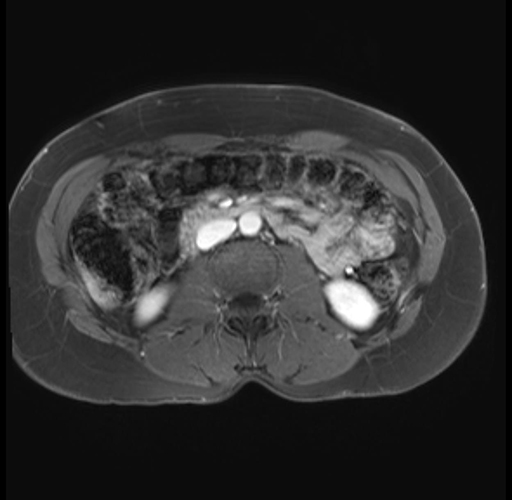

Imaging Analysis

Look through the patient's CT scan to identify any areas of concern for the necessary procedure.

Based on your CT findings, which issue(s) are present and would give reason for "planned slowing down moment(s)" in this case?